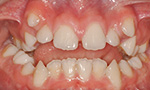

Die häufigsten Fehlstellungen

Nach Prüfung der Funktionen des Gebisses, wie zum Beispiel des Ineinanderpassens der Zahnreihen oder der Funktion des Kiefergelenks, steht fest, welche der folgenden Fehlstellungen vorliegt:

Unterzählige Zähne

Ein Zahn oder mehrere Zähne sind von Natur aus nicht angelegt.